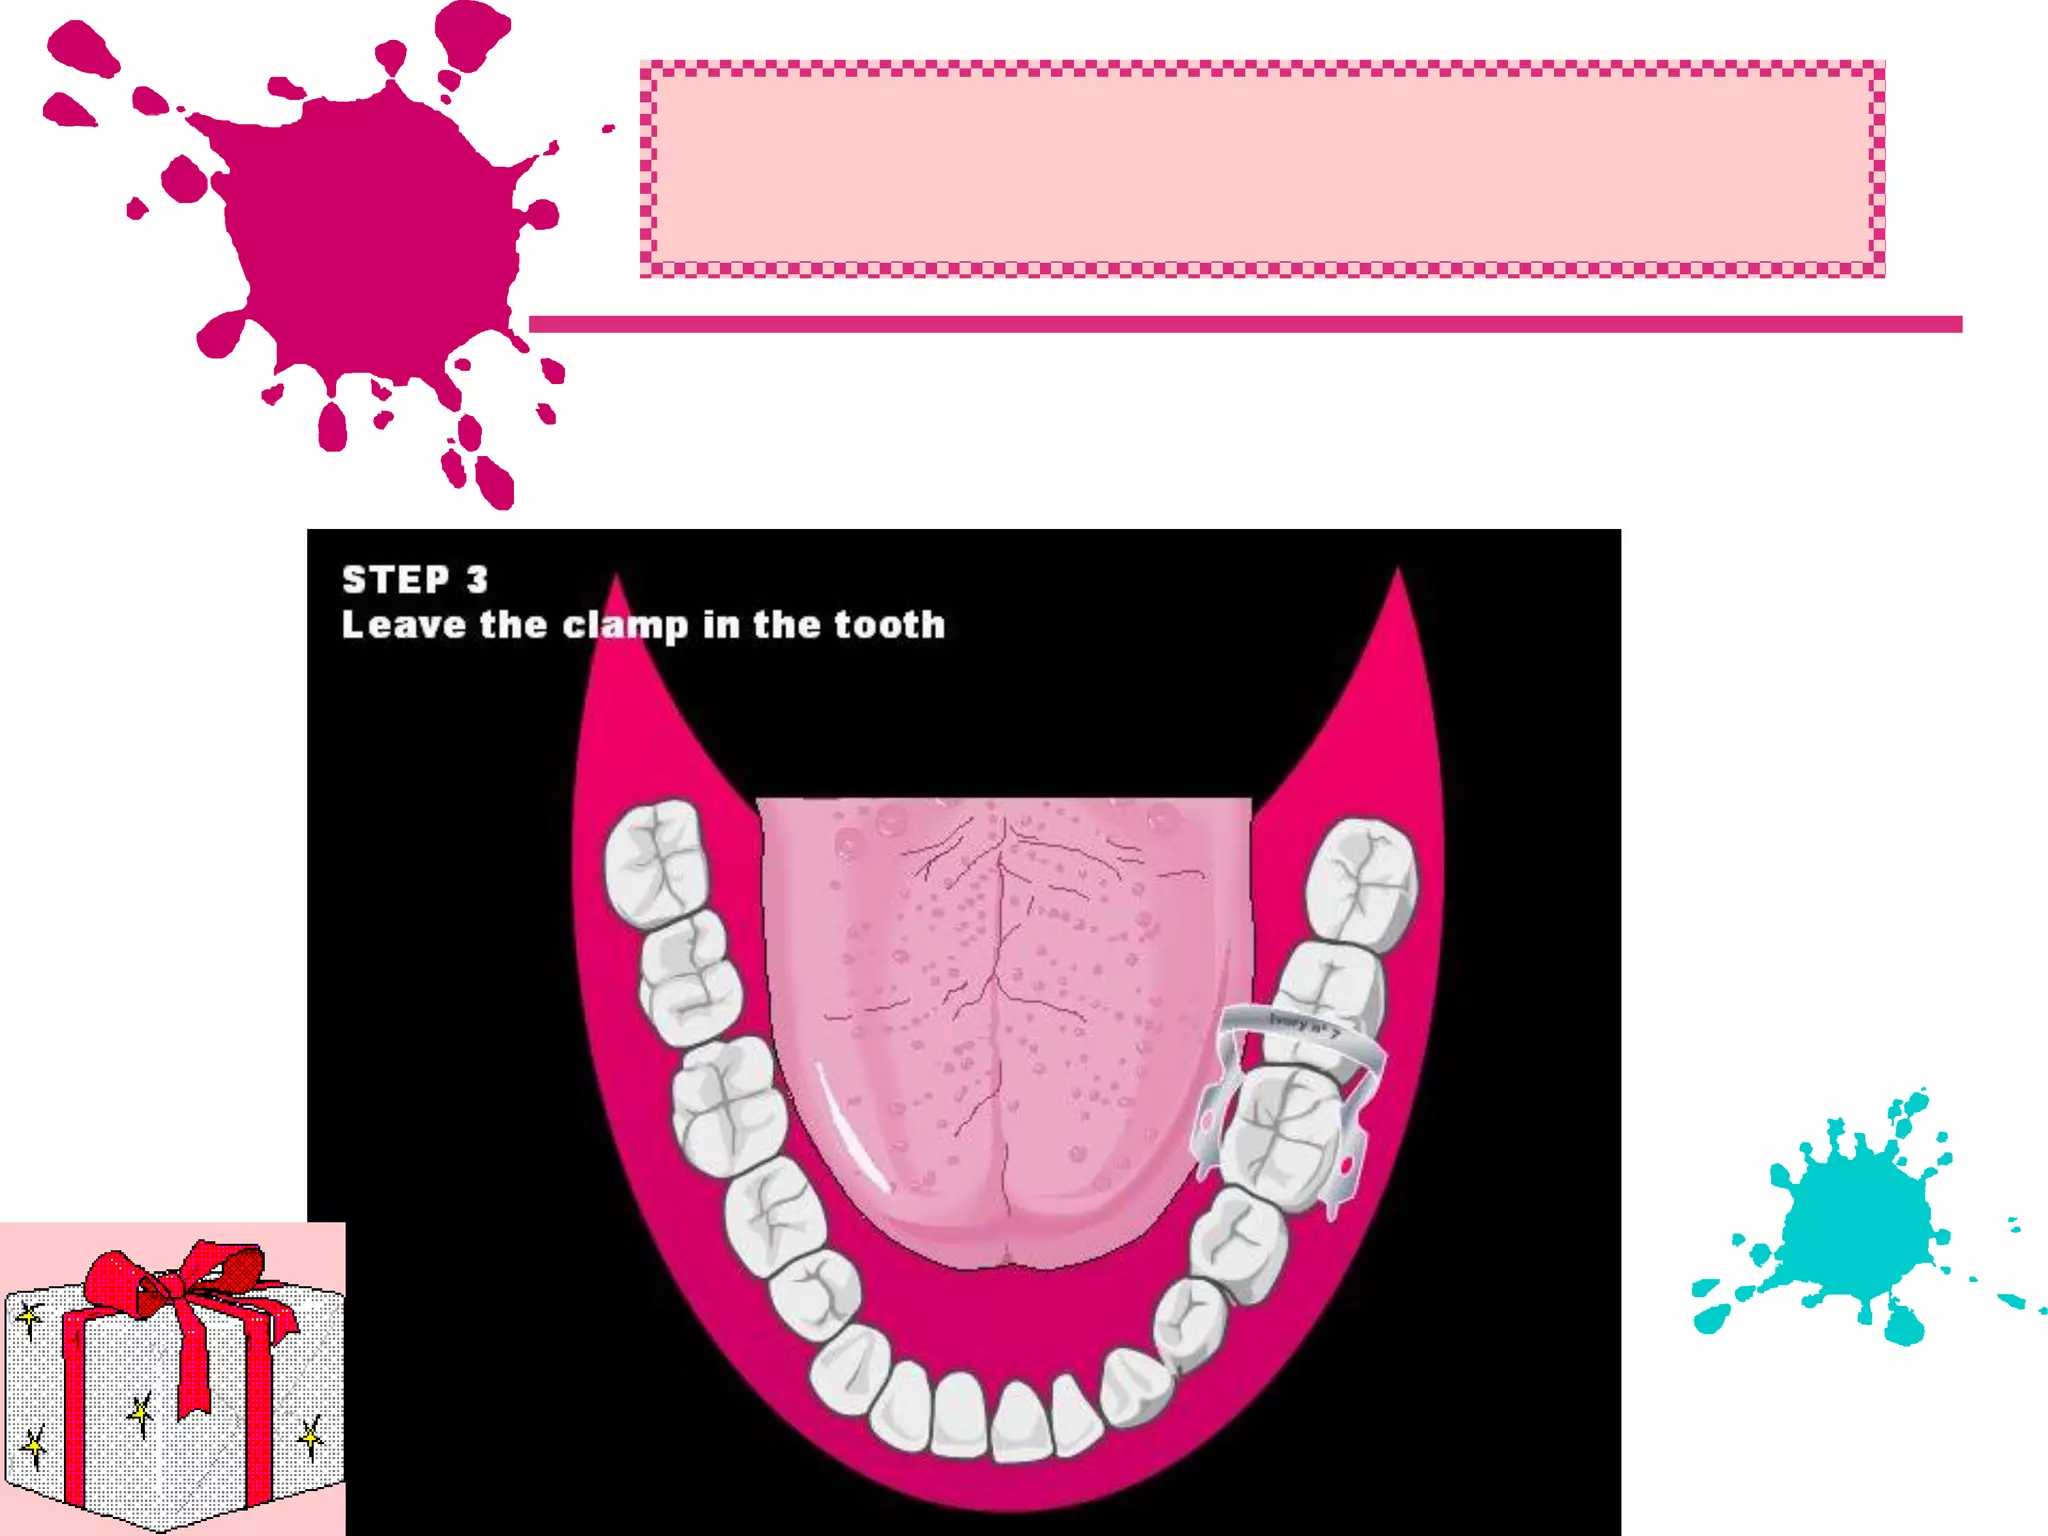

This document discusses the materials and components used for rubber dam isolation in dentistry. It describes the different types of rubber dam materials including color options and napkins to absorb moisture. It also outlines the tools needed such as punches to make holes, templates and stamps to guide hole placement, clamps to secure the dam, and other accessories like wedges and lubricant. Finally, it provides guidance on punching holes for different types of teeth and properly placing clamps in the rubber dam.